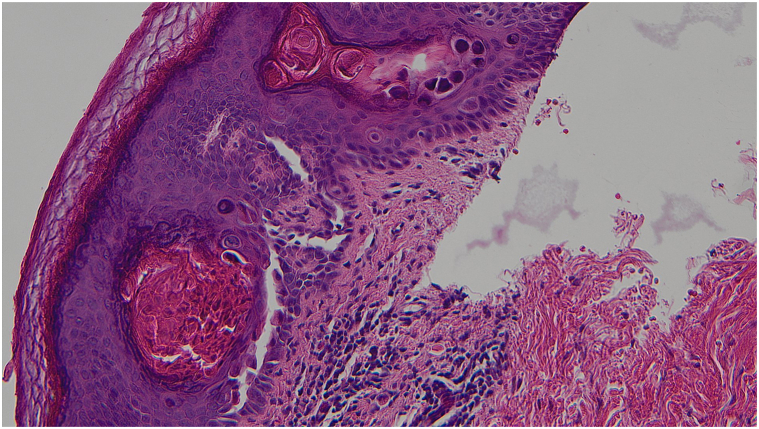

The initial histopathologic examination was done by a breast pathologist who only described a benign epidermoid cyst. The patient was referred to the dermatology clinic for management of the residual lesion. As the clinical presentation did not correlate with the diagnosis of an epidermal cyst, the slides were reviewed by a dermatopathologist with a corrected diagnostic of acantholytic dyskeratosis. With deeper levels cut in the biopsies’ cell blocks, the histopathologic examination demonstrated suprabasilar clefts in the epidermis with discohesive rounded keratinocytes (acantholysis). There was also dyskeratosis with 2 types of dyskeratotic cells, one type consisting of hypereosinophilic keratinocytes with pyknotic nuclei (corps grains) and the other type consisting of acantholytic keratinocytes with a larger nucleus and a perinuclear halo (corps ronds) (Figs 3 and 4). The skin appendages were spared by the acantholytic dyskeratosis.

Fig 4.

A higher magnification view of Figure 3. (Hematoxylin-eosin stain; original magnification: ×200.)